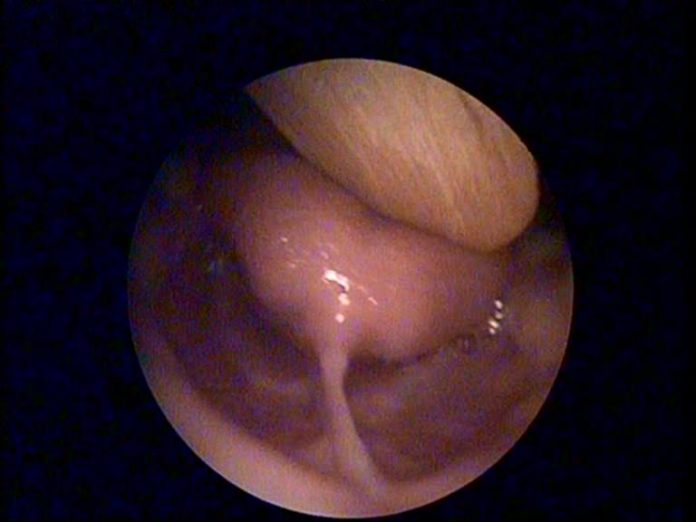

Günaydın. Zaman zaman anne babaları endişelendiren konulardan bir tanesi de dil bağı. Hepiniz bilirsiniz bazı bebeklerin veya çocukların dillerini çıkarıp yukarı doğru kaldırdıklarında ağız tabanı ile dil arasındaki Frenulum dediğimiz bağın normalden daha kısa olduğunu, biz buna dil bağında kısalık adını veriyoruz.

3 aşamada değerlendirmek gerekiyor. Öncelikle yenidoğan bebek sadece emiyor, konuşma yok ve de katı gıda yemiyor, çiğneme ve ciddi bir yutma fonksiyonu da yok. Dolayısıyla eğer ilk 6 ayda bebeğin emmesine, sütü yutmasına ve beslenmesine engel olmuyorsa dil bağına herhangi bir müdahale yapmamak gerekiyor.

2. aşama: 6 aydan sonra ek gıdalara geçiş ile birlikte katı gıdaların yenmesi, çiğnenmesi ve yutulması konusu devreye giriyor. Eğer bu aşamada çocukta yine herhangi bir beslenme sorunu yoksa rahatça çiğneyip yutabiliyorsa yine dil bağının ellenmemesi gerekiyor.

3. aşama ise özellikle 18 aydan itibaren kelimelerin telaffuz edilmesi, 2 yaştan sonra da 2-3 kelimenin birleştirilerek cümle kurulması yani konuşma fonksiyonu geliyor ve bu yaşa geldiğinizde çocuğun kelimeleri telaffuzunda ciddi bir sorun yoksa yine dil bağının ellenmesi gerekmiyor.

Yani dil bağının kısa olması aslında çoğu zaman bir sorun değil. Ancak dediğim gibi ilk 6 ayda emzirmeye engel oluyorsa, 6 aydan sonra katı gıdaları çiğnemeye, yutmaya, beslenmeye engel oluyorsa veya 2 yaş civarında da konuşmaya engel oluyor, bazı kelimelerin telaffuzuna engel oluyorsa o zaman dil bağı kesilebilir. Çok basit bir işlemdir hatta lokal anestezi ile muayenehane, ofis koşullarında kolayca yapılabilen bir girişimdir.